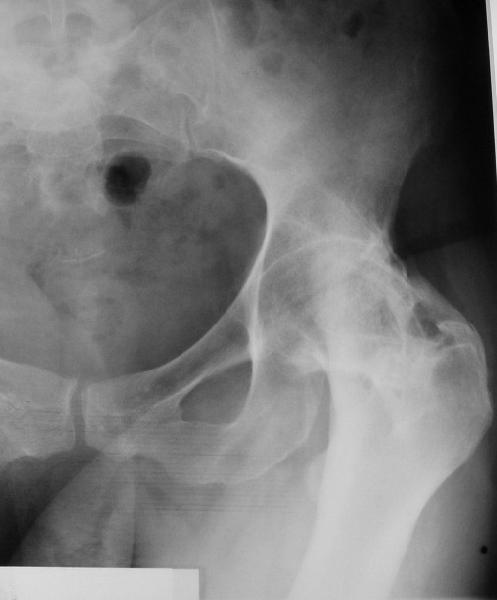

При обследовании выявлен анкилоз тазобедренного сустава в приведении. Видимо, в период пребывания в тяжелом состоянии появились гетеротопические оссификаты. За исключением того, что осталась одна почка, сейчас других медицинских проблем нет.

Пациентку в первую очередь беспокоят боли в спине, на отсутствие движений в суставе она вроде и не жалуется. Вопрос насчет тактики. Корсет и анальгетики вряд ли решение. Первый вариант - удаление оссификатов и эндпротезирование, второй - корригирующая остеотомия в проксимальном отделе с устранением порочного положения.

Боли в спине обусловлены порочным положением бедра. Эндопротезирование более интересно, т.к. дает еще и движения в суставе (кроме устранения порочного положения). Оссификаты не страшные, а учитывая срок (3 года) - уже созревшие. Я зарекся делать ЭТС при больших оссификатах - очень частый рецидив даже на фоне индометацина и луч.терапии.

Я думаю, что эндопротезирование - более предпочтительный вариант у пациентки 53 лет. К тому же суставная щель прослеживается и, вероятнее, большой сложности с установкой вертлужного компонента не будет. Высока вероятность необходимости аддуктотомии.

В любом случае замена сустава после оссификации дело не благодарное - безболезненная контрактура станет болезненной контрактурой.

После корригирующей остеотомии сохранится чрезмерная нагрузка на поясничный отдел за счёт анкилоза т/бедр. сустава.На фоне остеохондроза,спондилёза,спондилоартроза и спондилолистеза устранение порочного положения не избавит от болей и вряд-ли даже уменьшит их.Мне кажется тут нет альтернативы эндопротезированию.Но даже в этом случае не исключено,что позднее, на повестке появится необходимость вмешательства на позвоночнике.